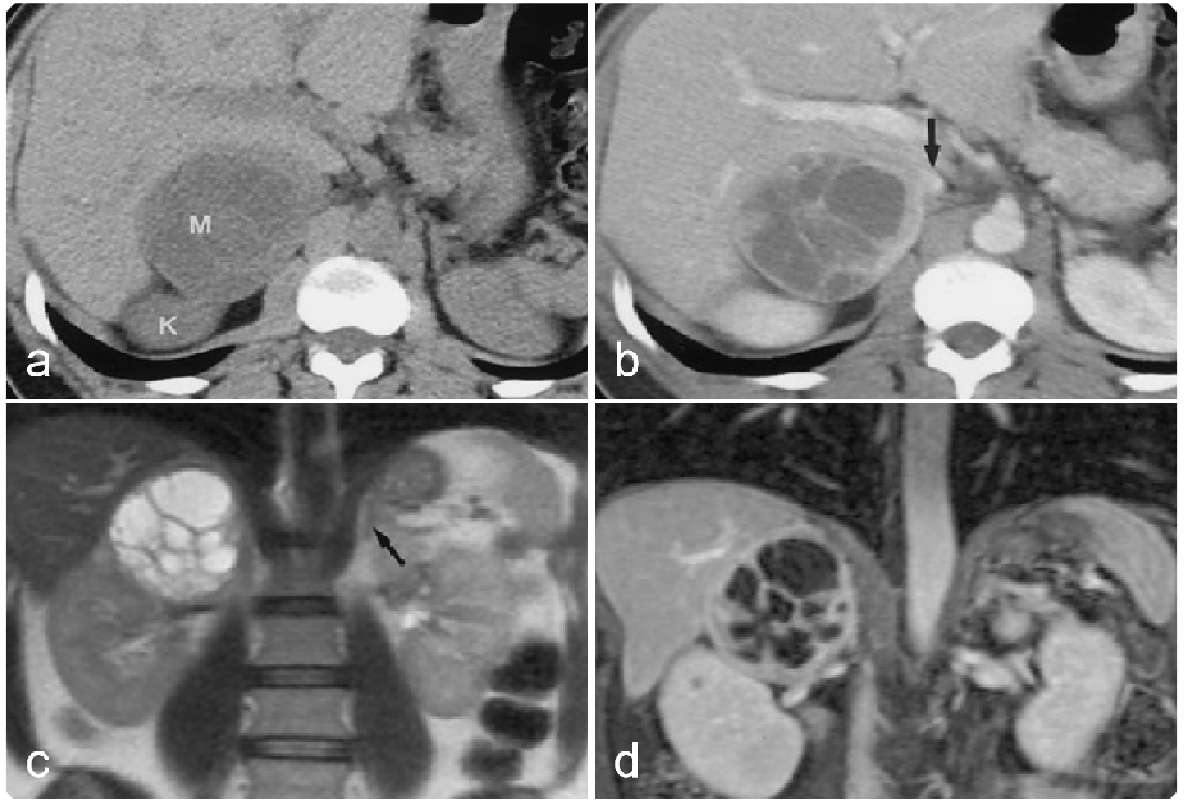

1cb7d55c23391da302d7e07c1a739bf1.png 图 44:神经鞘瘤(各部位)MRI典型征象a:“包膜下囊变征”,病灶包膜下多发大小不 、形态不定的无强化囊变区;b:“血管点征”,病灶内多发点状或管状的血管强化信号;c:“中央裂隙征”,病灶中心为裂隙状黏液变、囊变区;d:“束状征”,T2WI 示神经鞘瘤内及边缘多发条索状低信号神经纤维;e:“靶征”,T2WI 呈病灶外周高信号,中心等、低信号;f:“血管贴边征”;g1、g2:“典型靶征”;h1:“神经出入征”,MRN示神经鞘瘤的两极低信号A、B号神经出入;h2:箭头所指低信号的神经出入;i1、i2:“脂肪分离征”,病灶上下方小三角形脂肪信号,压脂后病灶上下方异常信号消失。